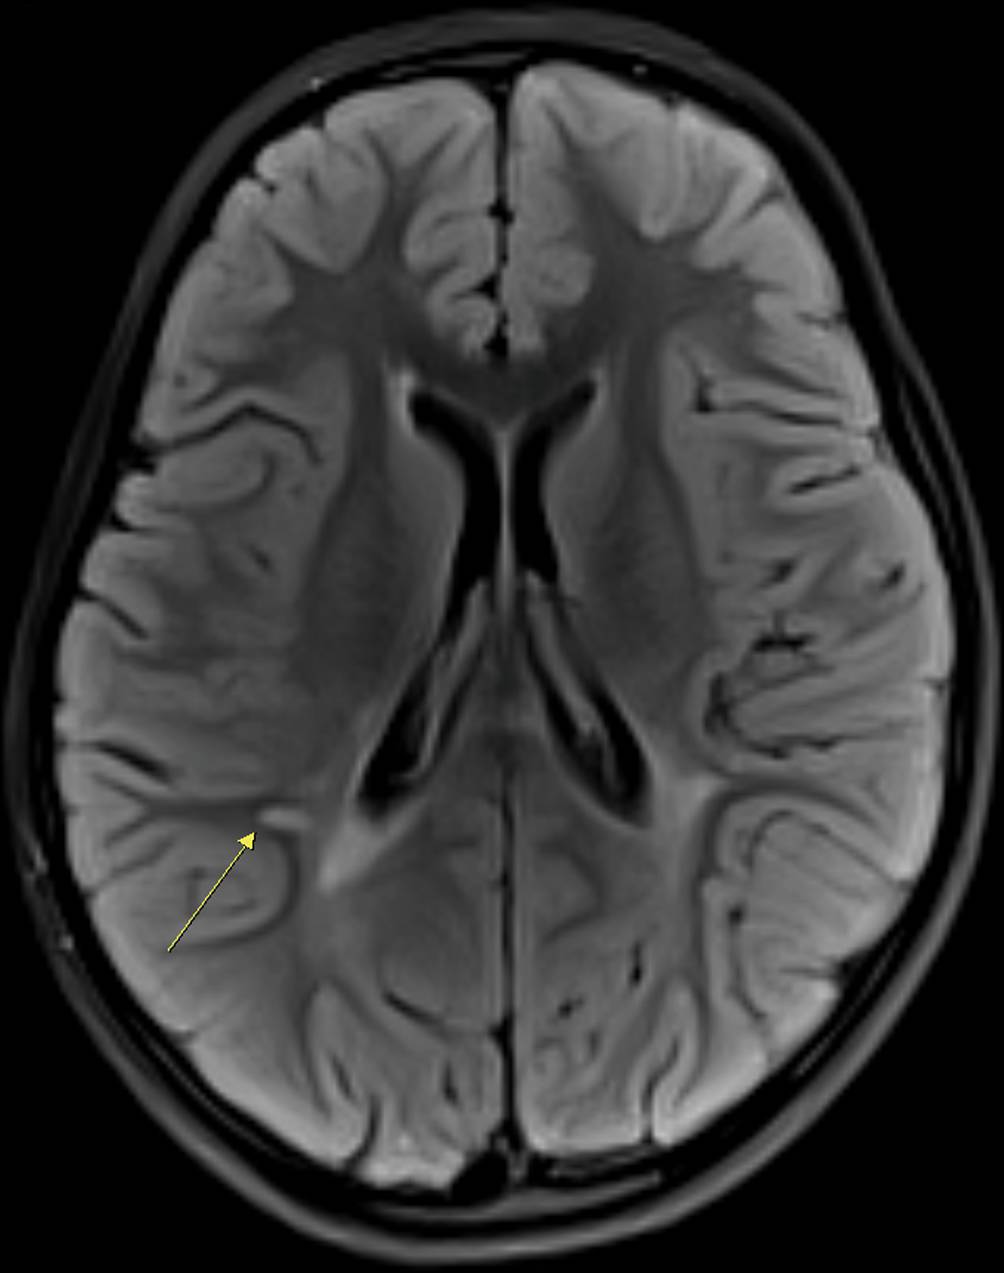

In der kraniellen MR-Tomographie ließen sich 10 periventrikuläre, 12 juxtakortikale sowie eine infratentorielle T2-hyperintense Läsion abgrenzen (Abb. 1). Davon zeigten 2 Läsionen eine Kontrastmittelanreicherung (Abb. 2). Die MRT-Untersuchung des Spinalkanals war unauffällig.

Abb. 2

T1-gewichtete cMRT-Aufnahmen mit kontrastmittelaufnehmenden Läsionen juxtakortikal (a) und infratentoriell (b)

Präsentation einer besonderes interessanten Patientengeschichte eines 8‑jährigen Mädchens mit plötzlich aufgetretenem partiellen neurologischen Ausfall des III. Hirnnervs. Der zusätzlich bestehende vertikale Nystagmus deutet auf eine über das Kerngebiet des N. oculomotorius hinausgehende, mesenzephale Affektion (Abb. 2). Wegen des erstmaligen Auftretens der Symptome wurde u. a. an eine akute Infektion und an eine akute disseminierte Enzephalomyelitis (ADEM) gedacht. Gegen Letztere spricht das Fehlen eines enzephalopathischen Geschehens. In der MR-Tomographie wurden entsprechend den revidierten McDonald-Kriterien die räumliche Dissemination (T2-hyperintense Läsionen in mindestens 2 der 4 typischen Regionen) und die zeitliche Dissemination (gleichzeitige Präsenz von Kontrastmittel-(Gadolinium)-aufnehmenden und Nicht-Kontrastmittel-(Gadolinium)-aufnehmenden Läsionen) nachgewiesen [1, 2]. Die zeitliche Dissemination wurde ferner durch den Nachweis oligoklonaler Banden bestätigt [2]. Somit sind die bildmorphologischen, klinischen und Liquorbefunde eindeutig mit der Diagnose multiple Sklerose vereinbar.